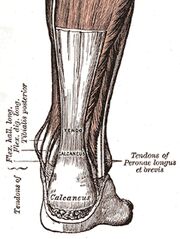

| 12:52, 14. Jan. 2011 | Achillessehne.jpg (Datei) |  |

120 KB | USykora | '''Achillessehne'''<br> Bildquelle: commons.wikimedia.org <br> Autor: Gray's Anatomy | 1 |